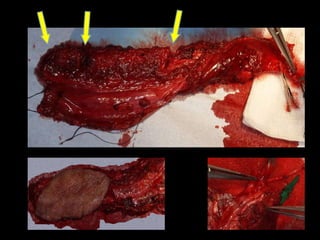

La oncología es una de nuestros mayores retos dentro de nuestra especialidad donde la cirugía ablativa y la cirugía reconstructiva se enfrentan. Cirugías de alto coste: para el paciente, el equipo quirúrgico, el hospital y el sistema sanitario. El acceso a biomodelos nos permitió la exploración de su uso y su utilidad.

Mejor planificación estética Y funcional mandibular en el auto trasplante de tejidos. Disminución del tiempo quirúrgico en el modelado de la placa mandibular 60´. Mantenimiento de la relación céntrica. Mayor exactitud con la “técnica en espejo”.

Evitar contaminación de campos. Mayor eficiencia al planificar y realizar las osteotomías mandibulares. Mayor eficiencia al planificar y realizar las osteotomías del peroné.